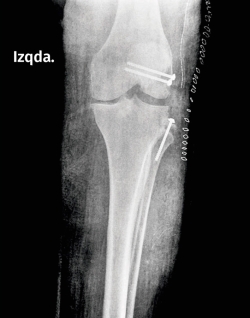

Se reparó quirúrgicamente el ángulo posteroexterno a los 10 días de la lesión. Se reinsertó la avulsión ósea del cóndilo femoral lateral con 2 tornillos canulados, de 4 mm, y del peroné, con un tornillo canulado del mismo diámetro. La paciente fue dada de alta a los 4 días con una inmovilización posterior (Figura 2).

Figura 2. Tratamiento: reinserción de la cabeza del peroné e inserciones femorales del tendón poplíteo y el ligamento colateral lateral.